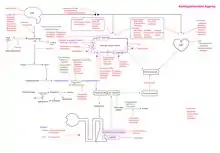

Pharmacological intervention

A meta-analysis of randomized controlled studies from 1970 to 2012 showed that lowering blood pressure via antihypertensive medications is associated with a reduction in heart failure and stroke risk.[27] Additionally, an Epidemiology of Vascular Aging (EVA) study showed that participants with high blood pressure exhibited 4 points lower on the Mini-Mental State Evaluation (MMSE) which correlates to these participants being 4.3 times more likely to exhibit cognitive decline and that the risk decreased to 1.9 times in those taking antihypertensive medication.[28] However, it is still up to debate on whether antihypertensive medications have an impact on cognitive decline. A randomized double blind study by the Systolic Hypertension Study in Europe revealed that the incidence of dementia was lowered by 50% in participants that were given pharmacological intervention for hypertension after 2 years and that there was a 55% decrease in the individuals developing Alzheimer's disease and vascular dementia.[29] The pharmacological drugs included nitrendipine (calcium-channel blocker), enalapril (ACE inhibitor), and hydrochlorothiazide (diuretic). Various studies looking at different classes of antihypertensive medication including ARBs, beta-blockers, diuretics, and ACE inhibitors, reveal that pharmacological treatments have overall cerebroprotective effects however, the effects vary depending on drug class and its mechanisms.[30][31][32]

Angiotensin-converting enzyme inhibitors

Angiotensin-converting enzyme (ACE) inhibitors essentially block the conversion of Ang I to Ang II. They cause relaxation of the blood vessels as there are less Ang II molecules (vasoconstrictor) circulating, increase natriuresis, decrease blood volume, all of which culminate in lowering blood pressure. Enalapril, Benazepril, Perindopril, and Ramipril are among commonly prescribed ACE inhibitors clinically.

Angiotensin receptor blockers

Angiotensin receptor blockers (ARBs) antagonize the action of Ang II by binding and inhibiting angiotensin II type 1 receptor. In doing so, ARBs block vasoconstriction, promote natriuresis, and reduce oxidative stress. Studies show that the vasodilator ability of vessels are impaired in hypertensives which causes brain perfusion to decrease significantly, influencing cognitive function. ACEs and ARBs improve cerebral perfusion in hypertensive patients.[31] Losartan, Irbesartan, Valsartan, Olmesartan, and Azilsartan, are common ARBs that are clinically available.

Angiotensin type 2 receptor agonists

AT2R agonists cause vasodilation, exerting hypotensive effects. In animal models of ischemia, activation of AT2R is protective as it reduces the infarct area by increasing cerebral perfusion, decreases superoxide production, and promotes neuronal cell differentiation and neuritis growth, which all come together to reduce axonal degeneration and inflammation.

Beta-blockers

Beta-blockers are competitive antagonists of the adrenergic beta receptor, blocking the binding sites of epinephrine and norepinephrine. They lower blood pressure by a RAAS independent mechanism, reducing plasma renin activity and Ang II levels. Propranolol, Atenolol, Bupranolol, Timolol, are some examples of clinically available beta-blockers.